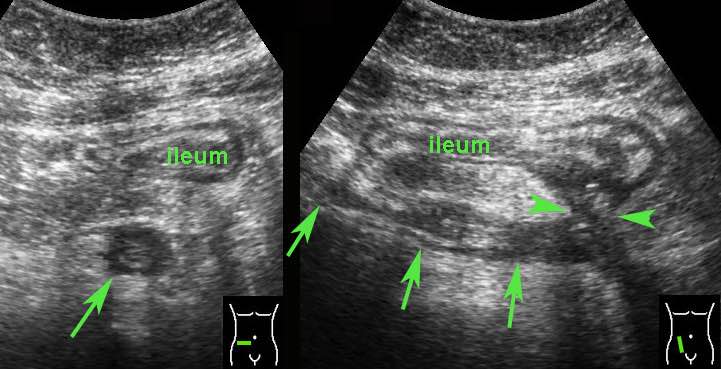

Một trong những đặc điểm của bệnh Crohn là cách thức tổn thương ruột theo từng mảng.

Điều này dẫn đến các tổn thương nhảy cóc, trong đó phần lớn đoạn ruột không bị ảnh hưởng.

Các đoạn bị tổn thương có ranh giới tương đối rõ, sự chuyển tiếp từ ruột bình thường (mũi tên nhỏ) sang ruột bất thường (mũi tên lớn) khá đột ngột.